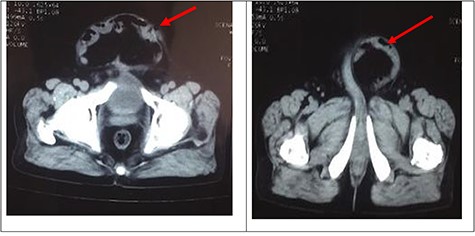

A palpable midline rectus defect of 10 cm was noted. Visible bowel peristalsis was seen. Other system examinations were normal. Routine laboratory investigations were normal, and he did not have any comorbid illness. Computed tomography (CT) of the abdomen confirmed thinning of the rectus sheath with focal outpouching of rectus in the infra-umbilical region and herniation of small bowel loops with loss of domain (LOD) (Fig. 2).

CT of the abdomen confirmed thinning of the rectus sheath with focal outpouching of rectus in the infra umbilical region and herniation of small bowel loops. Red arrows showing herniation of small bowel in infraumbilical region.